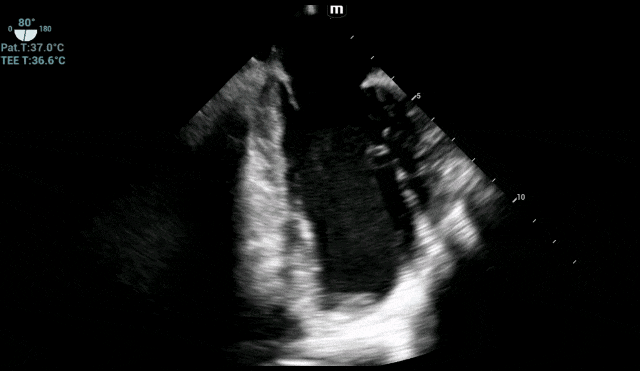

术中各时间段实时TEE监测心脏血栓情况

气腹与体位变动期:这是最易引起血压波动、心脏负荷变化的阶段。TEE实时显示心腔大小和收缩力的微妙变化,麻醉团队据此调整血管活性药物,将血压、心率牢牢控制在安全窗口内。

手术关键操作期:TEE始终锁定左心室,确认血栓无任何移位或脱落迹象,为外科医生创造了安心操作的环境。

在TEE的全程“导航”与麻醉科团队的严密护航下,手术顺利完成,患者安全返回病房。术后复查显示,心脏血栓稳定,患者恢复良好,未出现任何心脑血管并发症。